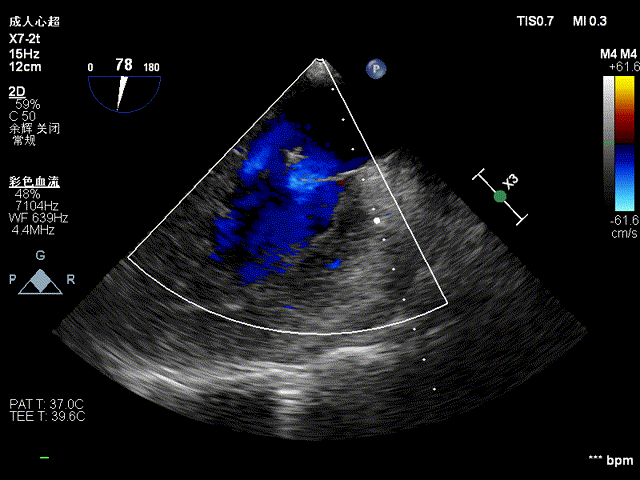

复查超声显示主动脉瓣架深度合适、位置稳定,瓣叶启闭正常,未见明显瓣周反流:

二尖瓣反流较术前显著减少:

彻底止血,闭合心尖和外周切口,手术圆满结束。